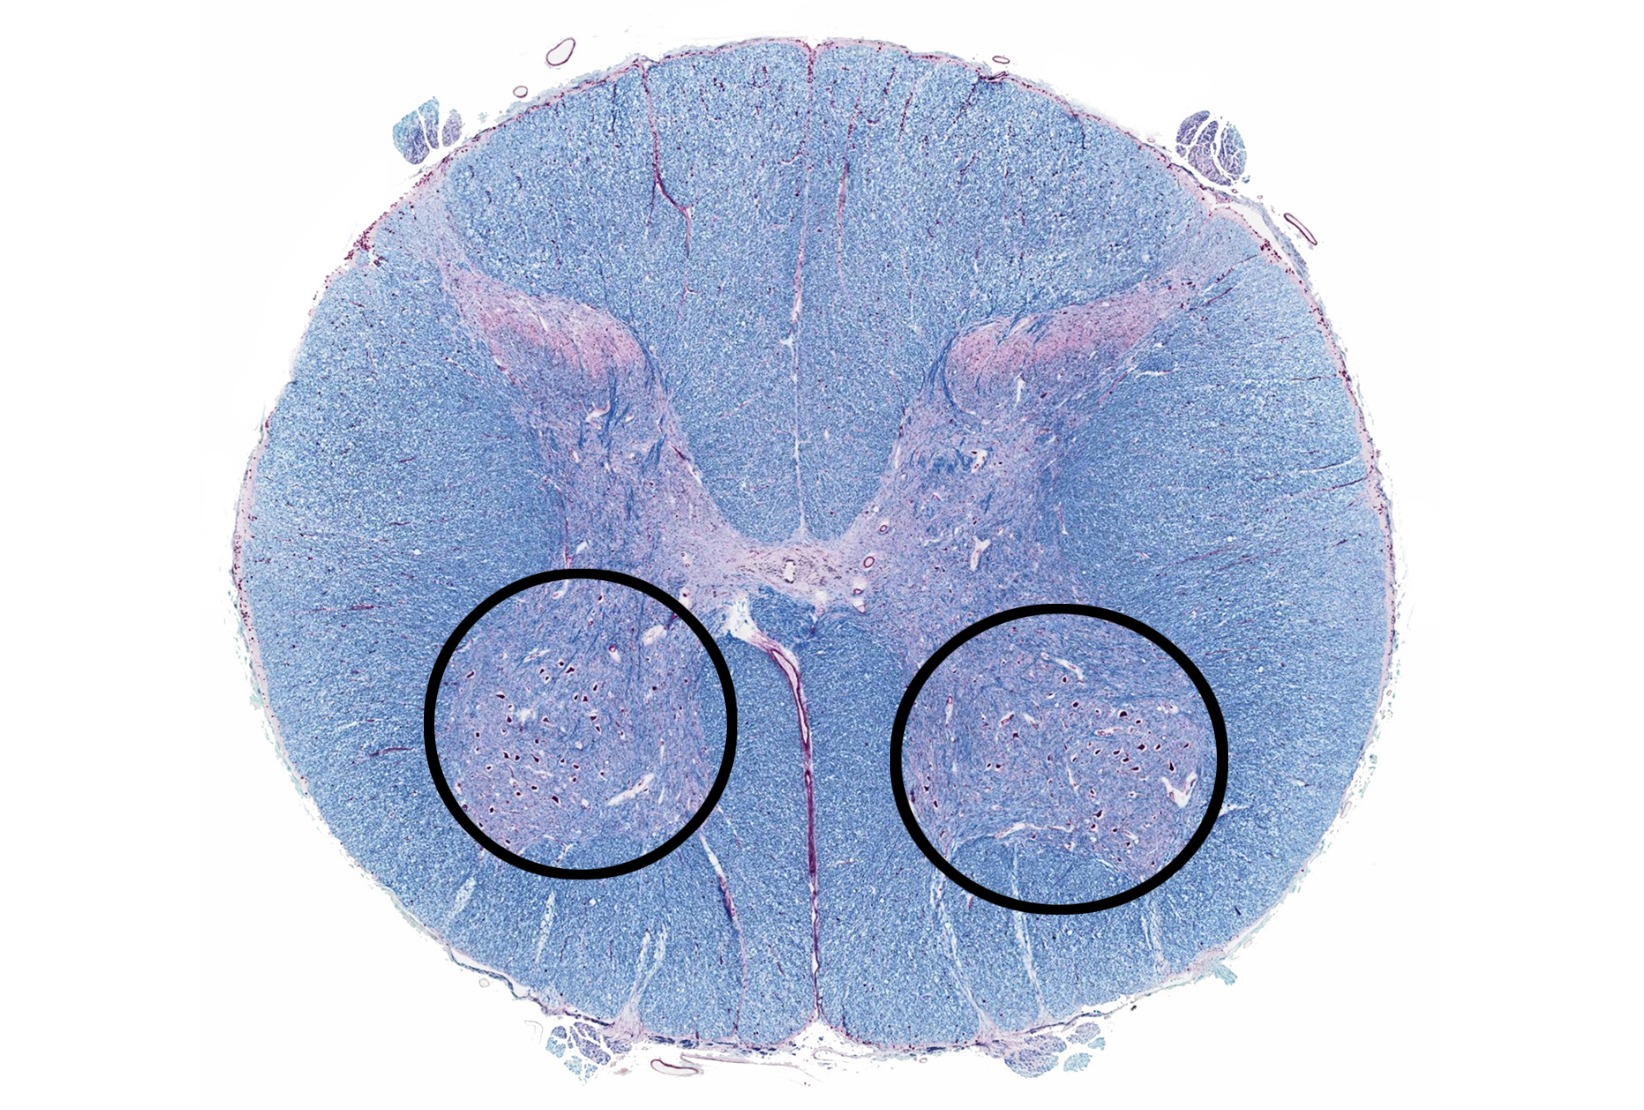

anterior horn